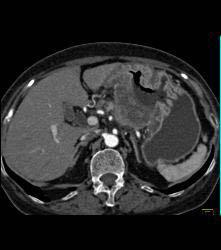

Antral Carcinoma With Adenopathy